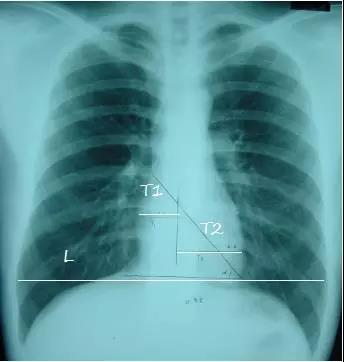

5.心影位置及大小

T1:心脏最右缘至前正中线距离

T2: 心脏最左缘至前正中线距离

L:通过膈肌顶部至两侧胸廓内沿并平行于膈肌的线

心胸比=(T1 T2)/L

1.正常<=0.50

2. 轻度增大 0.51-0.55

3. 中度增大0.56-0.60

4. 重度增大>=0.60